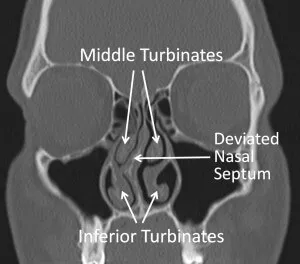

The nasal septum is the divider placed in the middle of your nose that separates the right and left nostril and nasal cavity. This divider is composed of both cartilage in the front and bone further back and is enclosed with a layer of mucosal tissue on either side of it. Think of it as a sandwich – on the inside of the sandwich resides the cartilaginous and bony elements of the septum; on the outside reside the mucosal layers. The septum ends beyond its bony portion and as a result, there is no division at the very backend of your nose, creating a single cavity or a common nasal airway at the very end of the nasal channels.

When the nasal septum “deviates”, it means the septum has begun to bend off-center and lean to one side of the nasal passage. Thus, it is commonly referred to as a “deviated septum.” Now, it is not uncommon for the nasal septum to lean on one side of the nasal cavity more than the other. As with our own bodies, we all have natural curves that are normal and define our body image. The same is true for the nasal septum. Either at birth or as you grow, the septum will develop its own curves along the way. It is rare to have a perfectly straight septum without some bends, whether it be minor or major. This is important to note because just because you have a minor deviation of your septum, it does not mean you have to do anything about it. In fact, many people are walking around with a deviated septum but have minor or no symptoms and thus, nothing needs to be done about it. If your nasal breathing is unaffected and you are not bothered by it in any way, a deviated septum need not be addressed and you can leave well-enough alone.

The main symptom associated with a deviated septum is nasal obstruction or congestion, in which you have difficulty breathing through one or both sides of your nose. This occurs due to a physical blockage. When the bend in your deviated septum is significant enough or severe enough that it is in contact with the other side of your nose, the passage of air through your nose is obstructed and, thus, you feel difficulty with nasal airway breathing. Other associated symptoms may include headaches or facial pain/pressure, sporadic nosebleeds, snoring, or sleep apnea. A deviated septum can also block your sinuses and cause sinus infections.